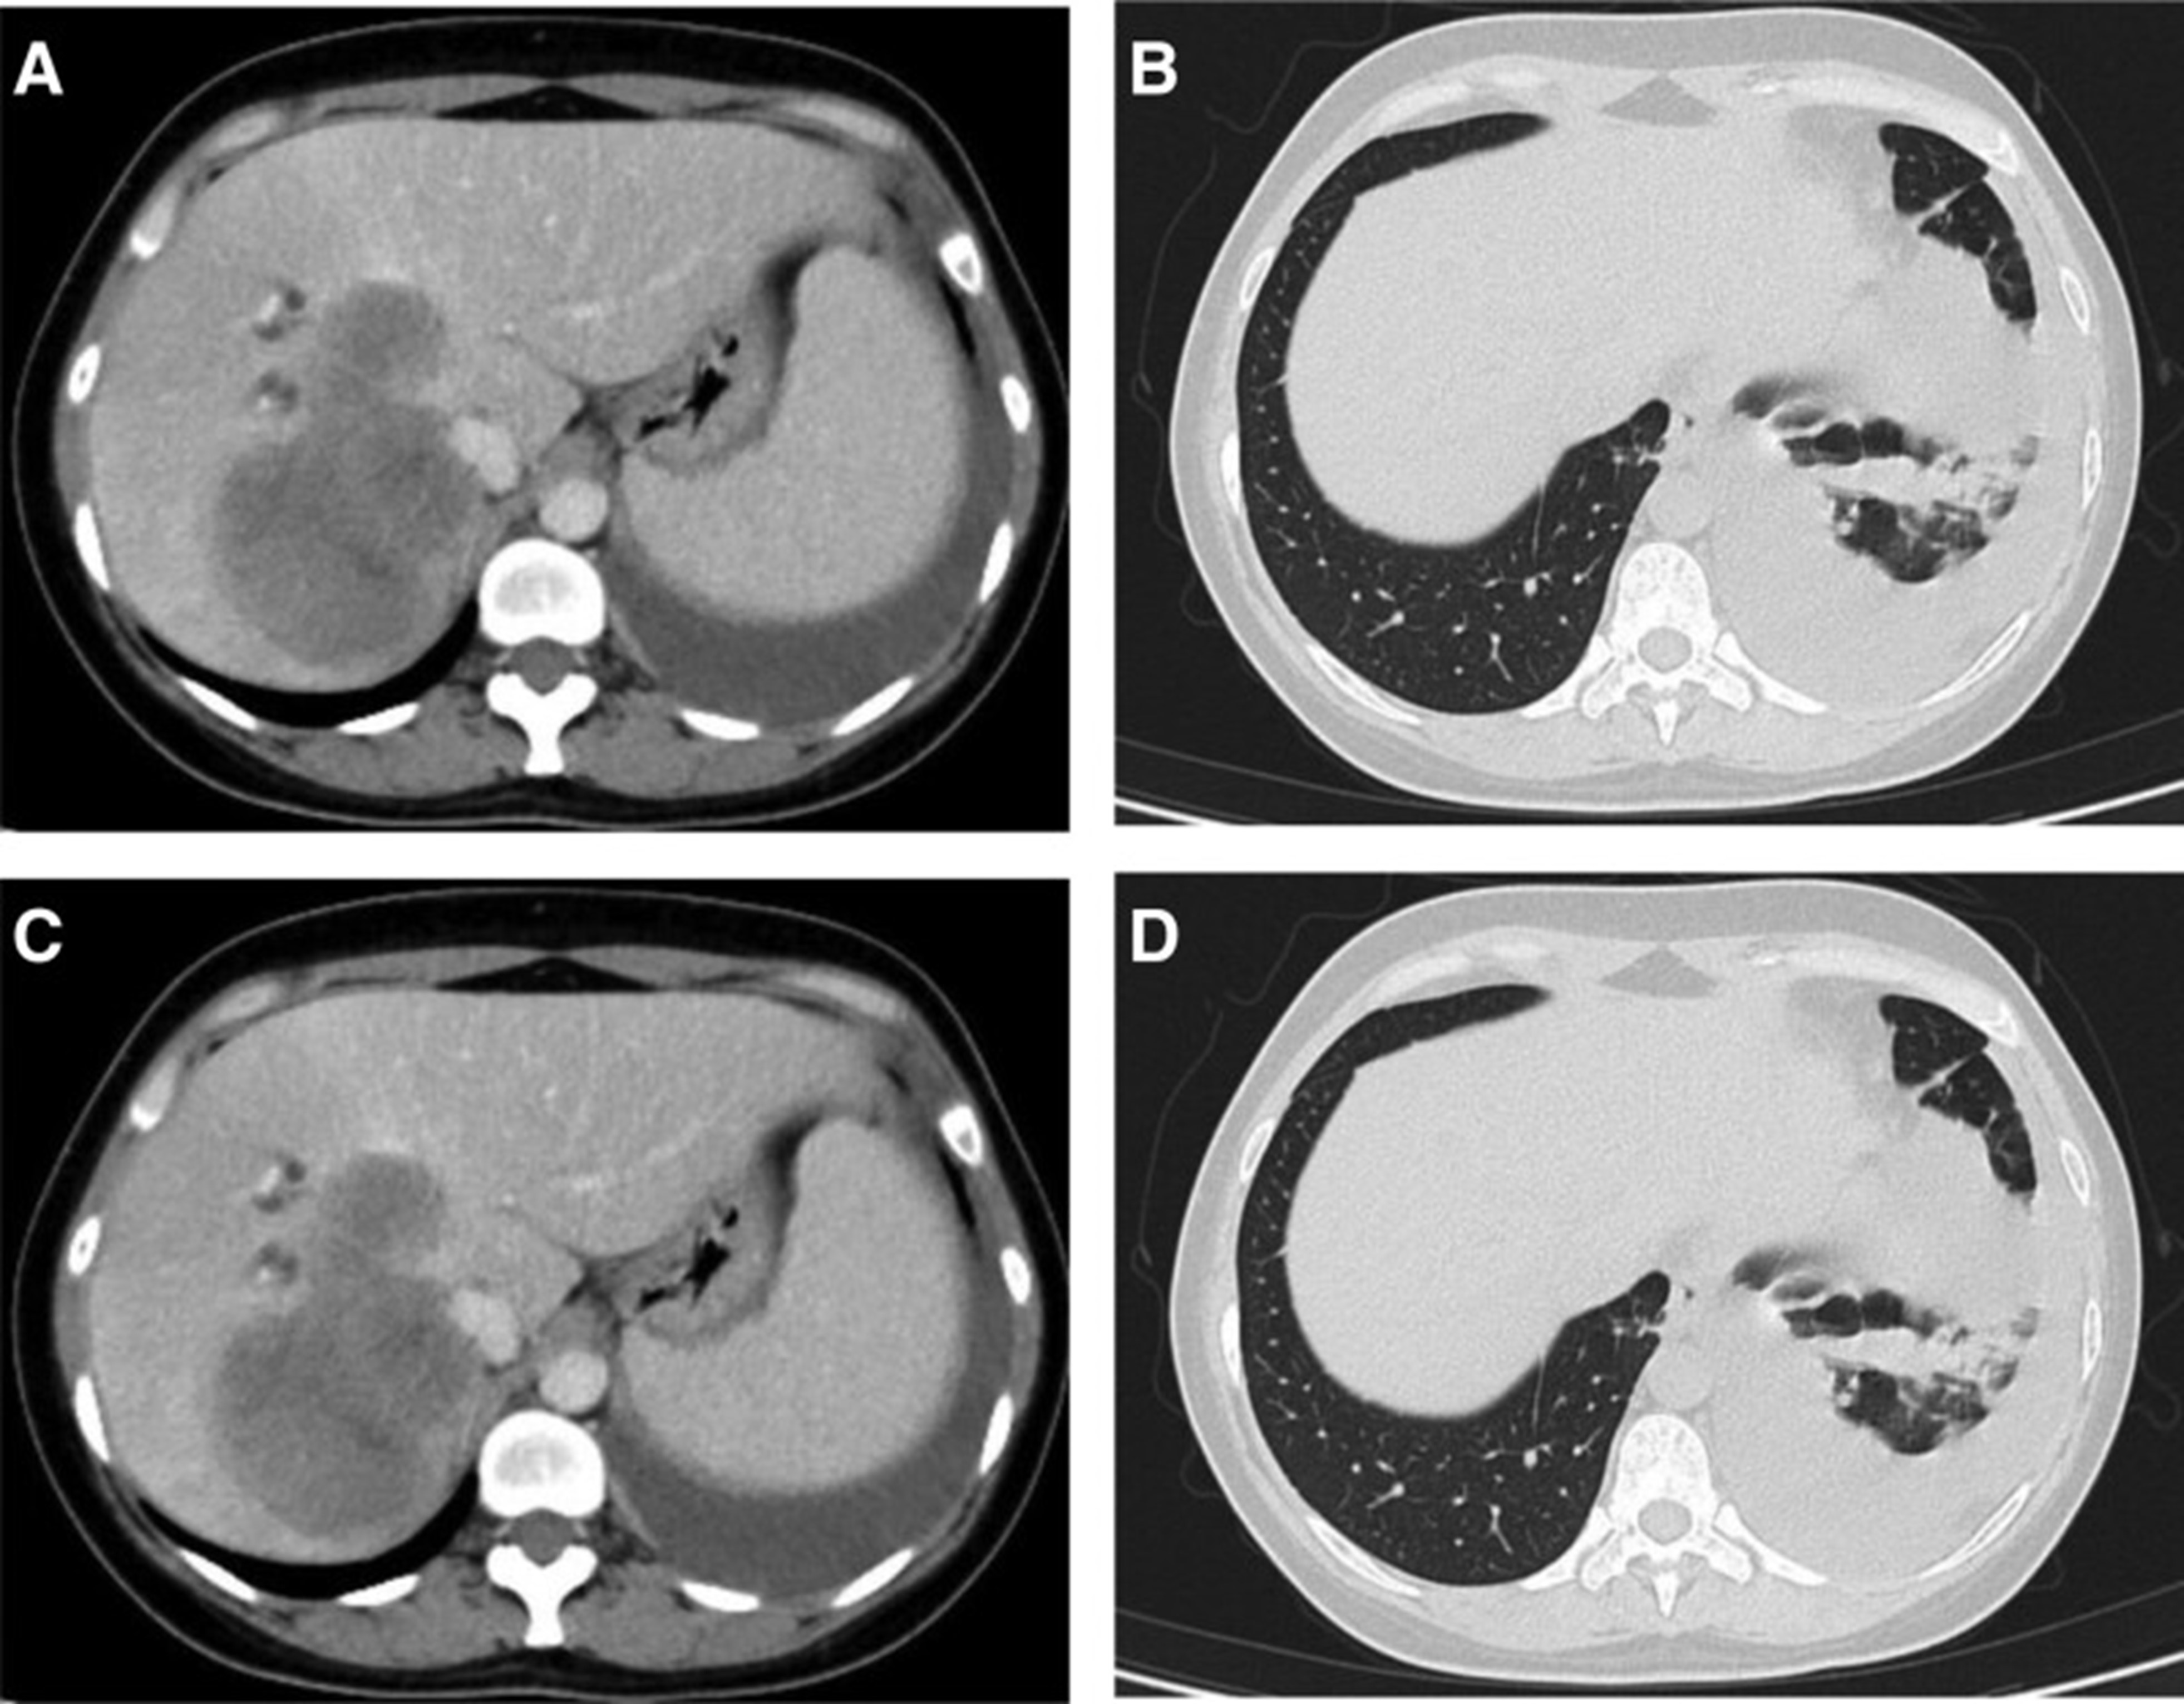

2020年5月1日,患者开始口服艾乐替尼靶向药物进行治疗,2020年6月25日复查,确定治疗效果为PR(部分有效)(根据RECIST1.1)显示肺病灶和肝转移灶明显减少(图1)。(图 3D-F)。2020 年 8 月 27 日复查确定治疗效果为疾病进展(PD, progressive disease),根据 RECIST1.1显示肝脏病变变大(图 1)(图 4A-D)。进行了第二次肝活检,随后的病理学显示“(肝)低分化癌,结合免疫组织化学分析考虑肺腺癌转移”。组织活检进行了第二轮基因检测,结果显示“BRAFV600E 14.79%,EML 4-ALK fusion 14.47%”(图 1)(图 5)。2020年9月20日,对患者我以为用恩沙替尼联合达拉非尼靶向治疗。治疗开始后,患者出现明显发热、寒战、乏力和厌食。期间患者左侧出现大量胸腔积液,胸腔积液中脱落细胞为“非典型细胞,考虑为腺癌”。随后,该患者接受了 1 次胸腔内铂输注。

和 2020 年 8 月.jpg)

图 5:2020 年 6 月(A 和 B)和 2020 年 8 月(C 和 D)的 CT 扫描。CT = 计算机断层扫描。

1个月后复查显示肺部和肝内病变进展(图1)。(图 6A-C)(根据RECIST1.1),她的抗肿瘤治疗改为“培姆曲塞加卡铂和贝伐单抗”的治疗一个周期。2020年12月至2021年1月,再次改变患者的治疗方案,这次改为“劳拉替尼联合达拉非尼”靶向治疗。使用 PD 联合胸部和腹部 CT 评估疗效(图 1)。(图 6D-F)(根据 RECIST1.1)。患者无法耐受化疗、靶向治疗、IO 治疗或任何其他积极的抗肿瘤治疗。这是因为患者的一般情况较差,包括发烧、腹痛和胆红素水平升高等症状。随后,给予患者静脉营养、镇痛等对症支持治疗。患者于 2021 年 2 月 4 日去世,总生存期(OS)为 10 个月。

和 2022 年 1 月 (D-F) 的 CT 扫描.jpg)

图 6:2020 年 11 月 (A-C) 和 2022 年 1 月 (D-F) 的 CT 扫描。CT = 计算机断层扫描。